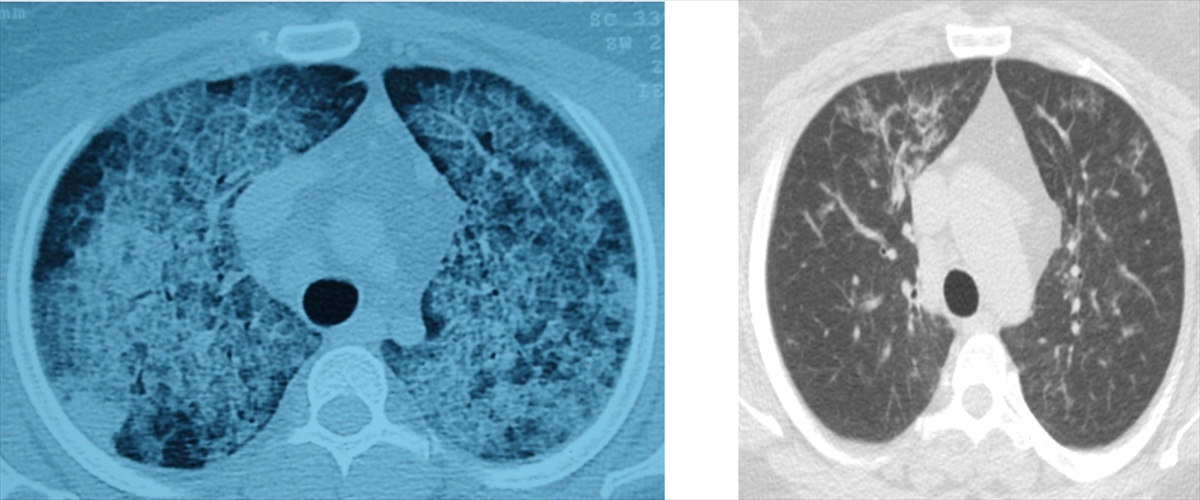

DENİZLİ (AA) - Pamukkale Üniversitesi Hastanesi’nde uygulanan akciğer yıkaması, nadir görülen akciğer hastalıkları için etkili bir tedavi yöntemi olarak dikkat çekiyor. Göğüs Hastalıkları Ana Bilim Dalı Öğretim Üyesi Prof. Dr. Göksel Altınışık Ergur’un öncülüğünde gerçekleştirilen çalışmalar, hastaların yeniden sağlıklı nefes alabilmesine imkan tanıyor.

Akciğerlerde yağ birikmesiyle ortaya çıkan bu hastalık, kişinin kendi yağ ve proteinlerinin temizlenmesiyle görevli hücrelerdeki sorunlar nedeniyle gelişiyor. Belirtileri arasında nefes darlığı, yorgunluk ve aşırı halsizlik bulunuyor. Çoğu durumda astımla karıştırılan hastalık, ancak ileri tetkiklerle teşhis edilebiliyor.

Sadece deneyimli merkezlerde uygulanabilen bu tedavi ameliyathane koşullarında gerçekleştiriliyor. Her seansta hastanın uyutularak 15-20 litre steril su ile akciğerlerin yıkandığını belirten Prof. Dr. Ergur, bu işlemin titizlikle yapıldığını vurguluyor.

Bazı hastalar kendiliğinden düzelirken, bazılarında birden fazla seans gerekebiliyor. Prof. Dr. Ergur, "Yıkama sırasında sıvının koyu renginin giderek açılması, işlemin doğru yolda olduğunu gösterir. Bu sayede hastalar yeniden nefeslerine kavuşuyor." diyerek tedavinin başarısına dikkat çekiyor.